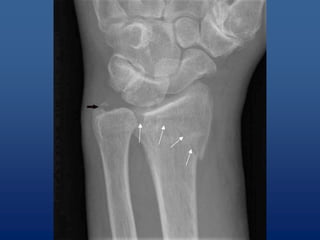

• Identifying fractures (cracks) and breaks or

infections in bones and teeth1

Uses of x-rays •Identifying fractures (cracks) and breaks or infections in bones and teeth1 • Diagnosing cavities and evaluating structures in the mouth and jaw • Picking up on signs of joint changes that indicate arthritis using a special type of X- ray image called an arthrogram • Revealing tumors on bones •